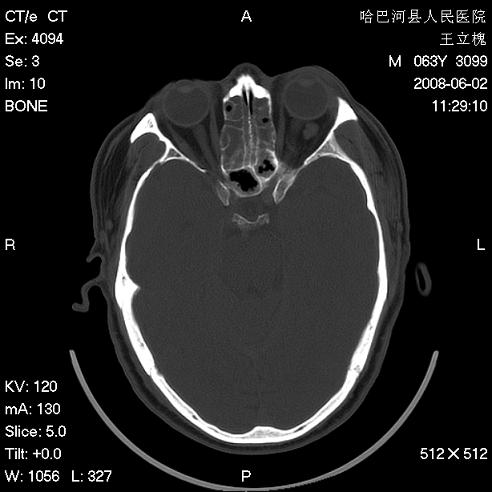

标题: CT13803:反复性鼻塞、流涕一年余 [打印本页]

标题: CT13803:反复性鼻塞、流涕一年余

副鼻窦炎,右上额窦积脓。左眼肌锥内见致密影,视神經受压

1.全组副鼻窦炎2.双侧上颌窦积液

全组副鼻窦炎 肌锥内高密度灶。建议进一步检察检查

2、左眼眶肌锥内病变,小血管瘤?建议增强。

1)全副鼻窦炎(左侧上颌窦黏膜下囊肿或息肉)。2)左眼眶肌锥内不规则小结节状软组织密度影;考虑为小血管瘤可能。建议行ct增强扫描检查。

全组副鼻窦炎,左侧肌锥内不规则形软组织肿块影,与眼外肌密度相当,左侧视神经受压,肿块与视神经及眼外肌分界清晰,眼外肌无增粗,眶壁无破坏,球后脂肪间隙不模糊,考虑良性改变,小血管瘤或神经源性肿瘤可能,建议增强扫描。

谢谢,增强扫描做了,眶内病灶与海绵窦同步明显强化,血管瘤